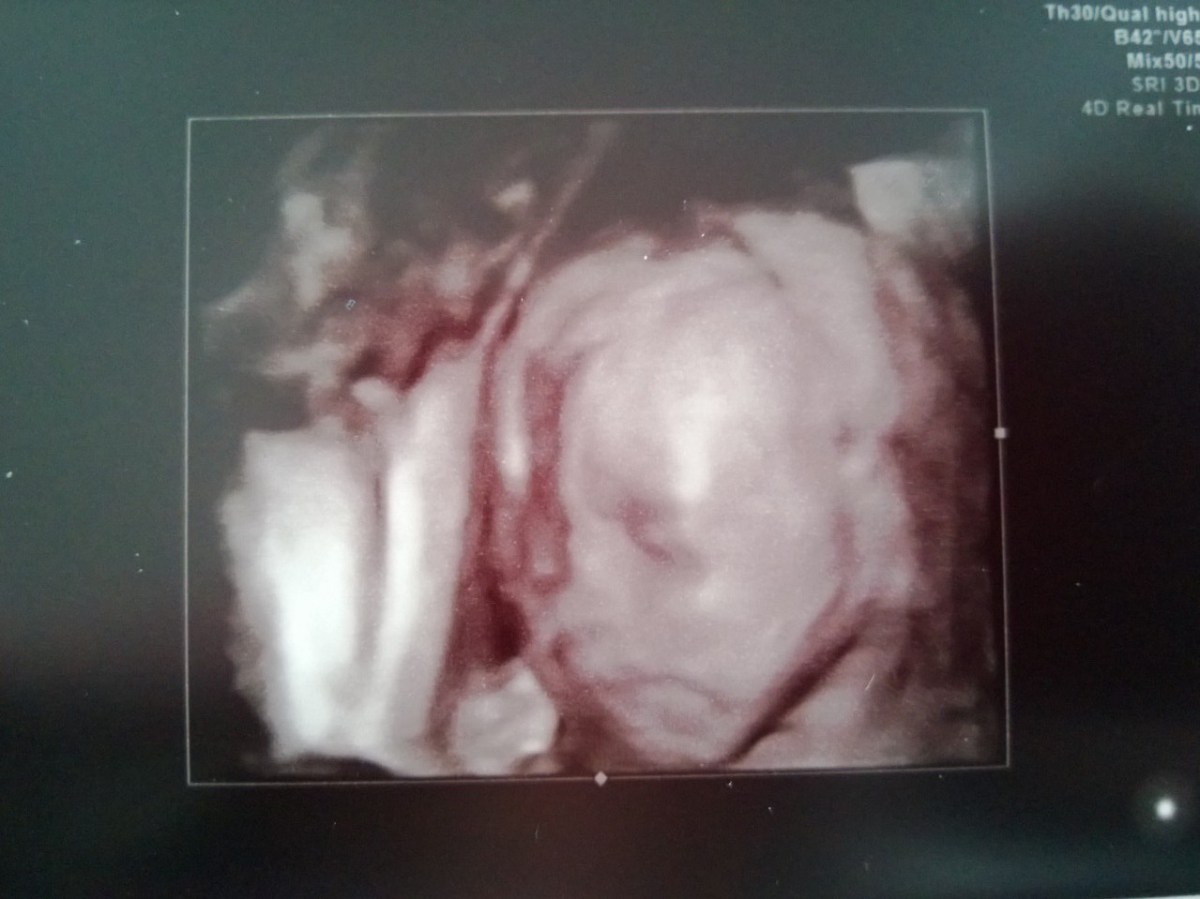

WP_20130222_014 February 22, 2013 by Courtney Leave a comment ← Previous Image Next Image → 21w6d Like Loading...